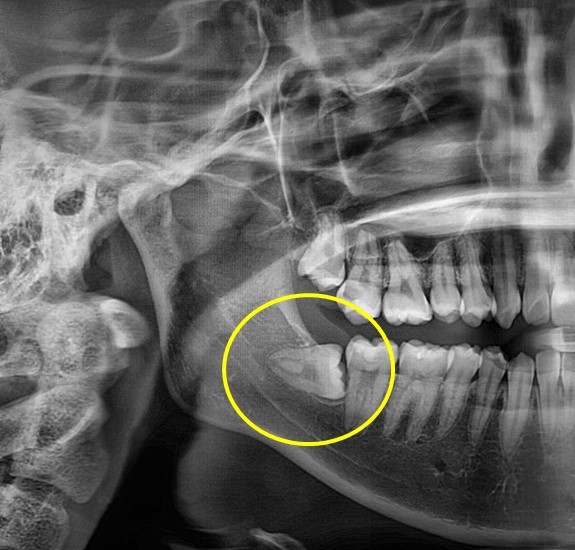

매복사랑니 발치사례